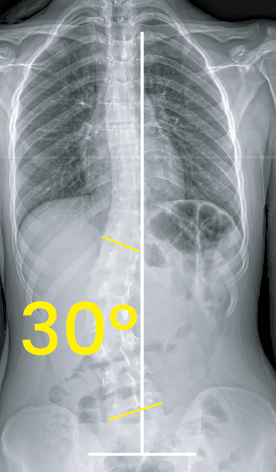

Omurga eğriliğini ve 30 derece açıyı gösteren iskeletin göğüs-karın röntgeni.Göğüs ve karın bölgesinin iki farklı açıyla çekilmiş röntgen görüntüsü ve üzerinde 8 derece açı gösteren sarı işaret.

Toraks röntgen görüntüsünde 30 derecelik skolyoz eğriliği sarı açılarla ve beyaz çizgilerle işaretlenmiş.Göğüs ve bel bölgesini gösteren röntgen, omurga eğriliğinin 14 derece olduğunu belirtir.